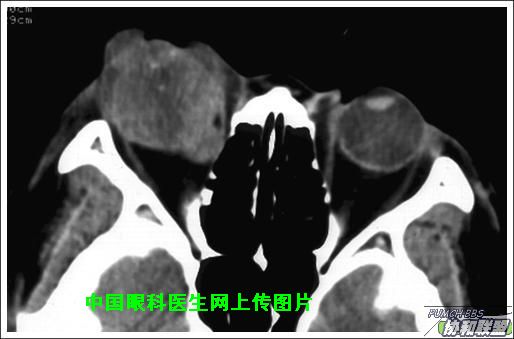

出院后半年发现右眼出现肿物,增长较快,随来京再次就诊(图1),转来我科。门诊检查发现:右眼无光感,结膜下肿物,突出睑裂。眼球突出,上移位。眶外侧可触及硬性肿物。超声(图2),CT(图3),MRI(图4,5,6)显示如图.